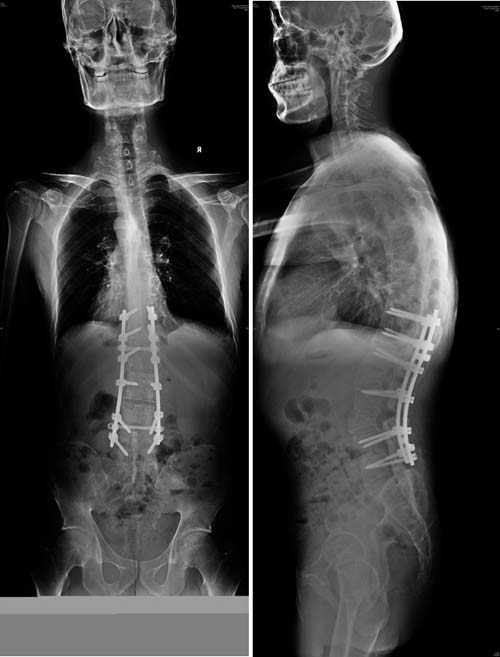

术后X线

术后,小刘的心肺功能得到了改善,营养状况得到提升。蒋振松团队为他制定了康复计划,并联系了血液科协助控制慢粒病情。小刘及其家属对矫形效果非常满意,对蒋主任及其团队高超的医术非常认可。